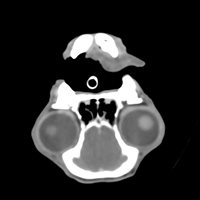

Massif facial

- Maladies parodontales, fistules Oro-Nasales (infections dentaires sévères)

- Exophtalmie ou dissymétrie de la face

- Douleur buccale, difficultés pour ouvrir ou fermer la gueule, trismus.

- Amyotrophie temporale (fonte musculaire)

- Syndrome de Claude Bernard Horner

- Pathologie rétrobulbaire

- Traumatisme facial

- Bilan d'extension des tumeurs de la face